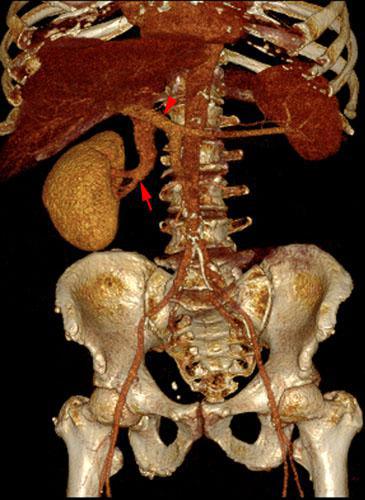

Agenesia Renal